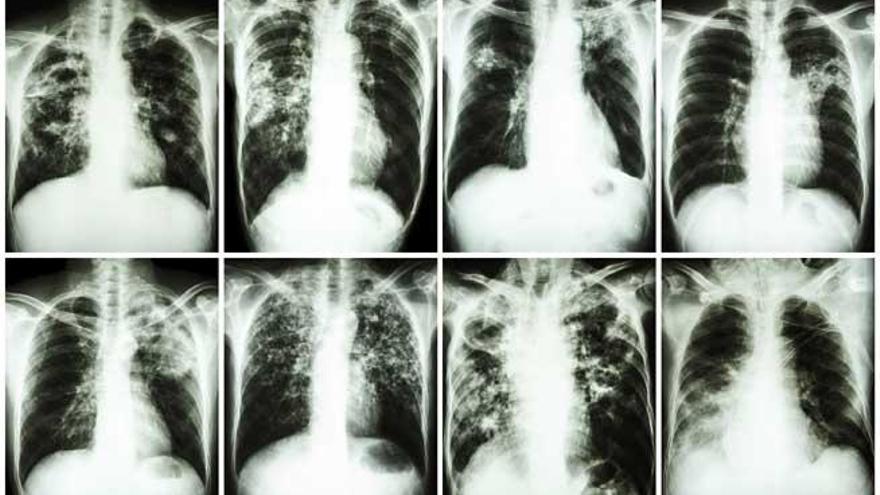

La tuberculosis afectó en 2014 a 9,6 millones de personas y causó 1,5 millones de muertes, según datos de la Organización Mundial de la Salud (OMS), que no obstante celebra que la mortalidad se ha reducido un 47% en los últimos 25 años, desde el año 1990.

De hecho, pese al descenso de la mortalidad, este organismo de Naciones Unidas reconoce que por el momento "la batalla sólo se ha ganado a la mitad" ya que cada día se siguen registrando más de 4.000 muertes por esta enfermedad infecciosa, que sobre todo afecta a las poblaciones más pobres y vulnerables.

La tuberculosis es junto al VIH la enfermedad infecciosa con más muertes a nivel mundial. Más del 95 por ciento de las muertes se producen en países de bajos y medianos ingresos y está entre las cinco principales causas de muerte en mujeres de 15 a 44 años. Además, se estima que en 2014 un millón de los casos de tuberculosis se dieron en niños, causando unas 140.000 muertes.